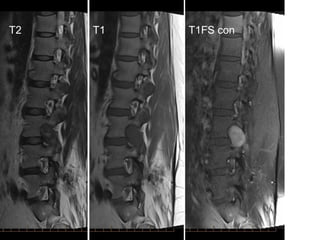

T2 T1 T1FS con